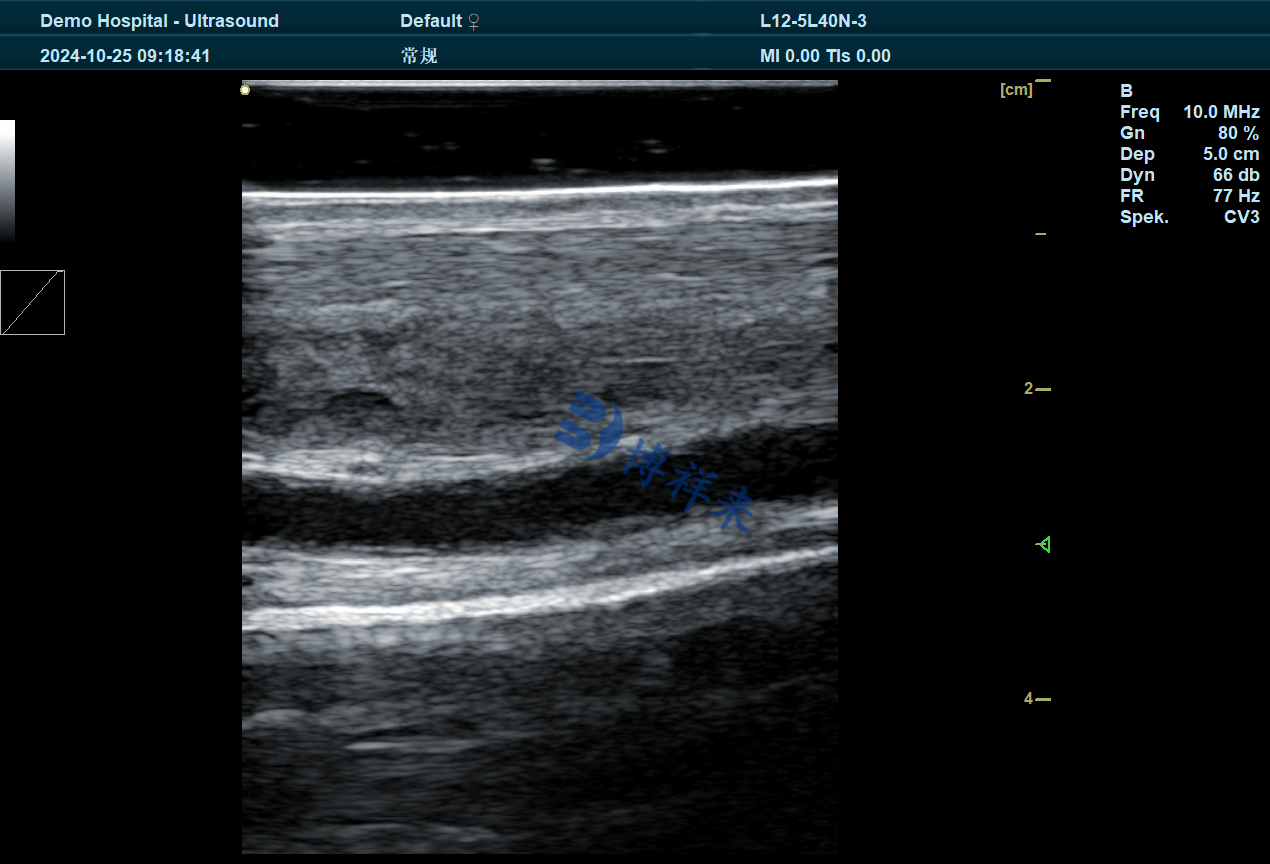

健康的肌腱或韧带在纵切面上表现为平行、均匀的高回声线条。

康复过程中,如果仍可见到低回声间隙或纤维紊乱,说明组织尚未完全重建。

测量受伤区域的截面积变化,若逐步缩小并接近健康对侧,即表明组织愈合良好。